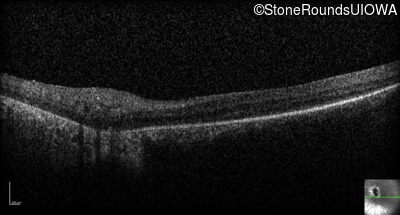

Optical Coherence Tomography - Right - 1/700 sc

Exemplar

Optical Coherence Tomography - Left - 1/700 sc